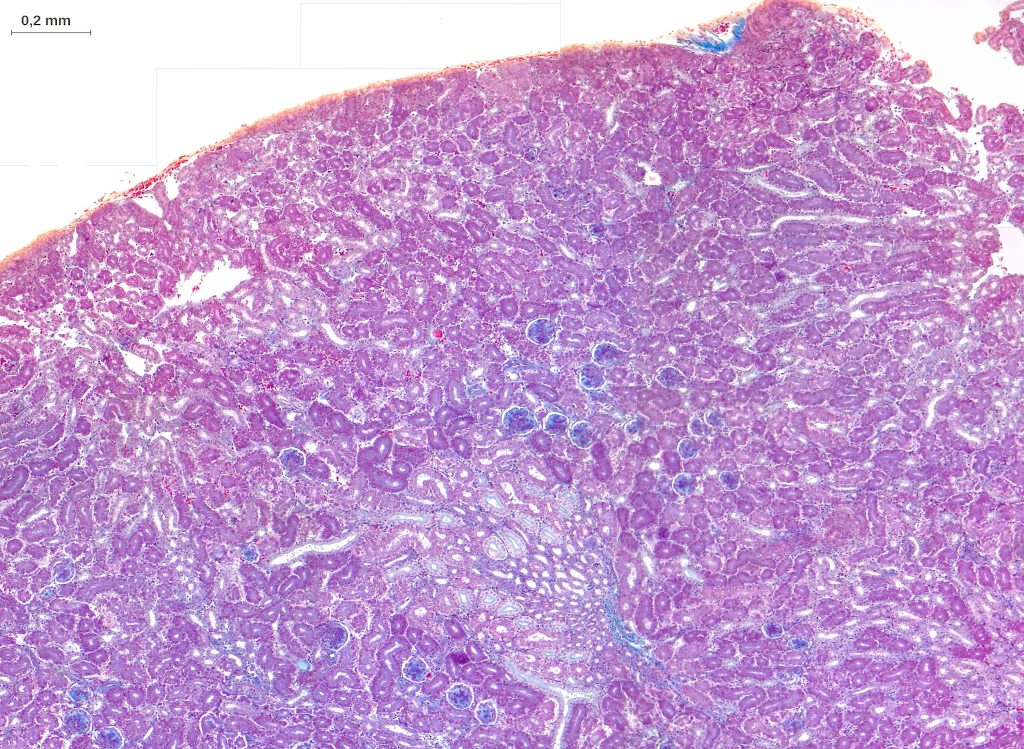

Une coupe histologique révèle que le rein de Poulet est formé d’unités appelées lobules, délimitées par du tissu conjonctif fibreux.

Chaque lobule est constitué d’une région périphérique, qualifiée de corticale, et d’une région centrale, dite médullaire.

Les régions médullaires des lobules voisins sont groupées et convergent en une structure conique ouverte sur l’uretère.

La région corticale des lobules comporte des corpuscules de Malpighi, des tubules contournés proximaux et distaux ainsi que des tubules collecteurs.

Leur région médullaire comprend des portions droites des tubules proximaux et distaux, des anses de Henlé ainsi que des tubes et canaux collecteurs, associés à des vaisseaux droits.

Ces structures sont entourées de tissu conjonctif fibreux constituant l’interstitum rénal.